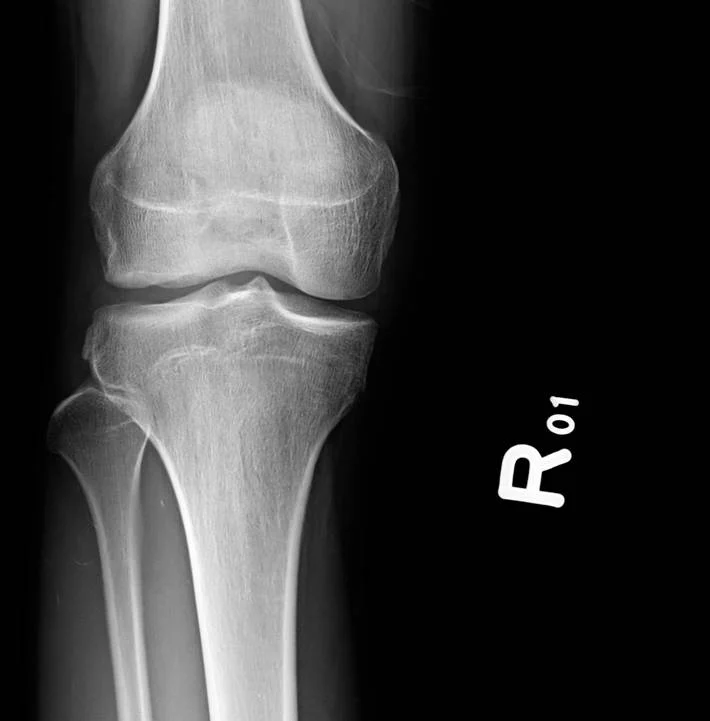

【110-1 醫學(六) 第73題】

20歲男性病患膝關節受傷,接受膝部X光及磁振造影檢查如圖,下列何者診斷為錯誤?